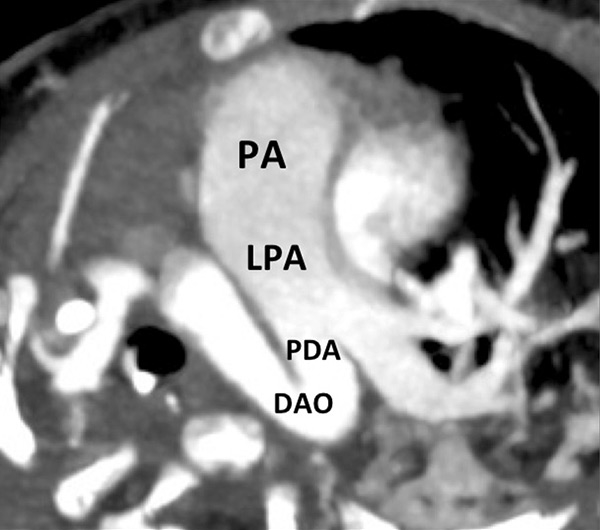

Figure 9

Pulmonary hypertension due to a patent ductus arteriosus (PDA) connecting the descending aorta (DAO) to the left pulmonary artery (LPA) (A) in a 2-month-old boy treated for a right diaphragmatic hernia (B) resulting in hypoplasia of the right pulmonary artery (arrow). The functional consequences (C) are extended hypoperfusion of the right lung (star).